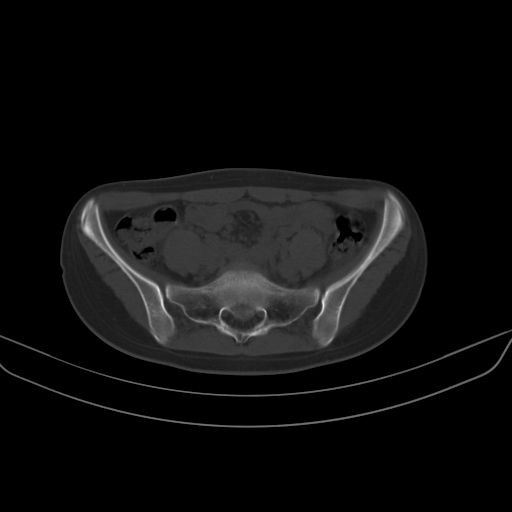

以下是引用子十在2008-7-11 21:12:00的发言:[br]考虑强脊

以下是引用zsl6918在2008-7-11 21:40:00的发言:[br]双侧骶髂关节骨质破坏以下三分之一为主,符合强直性脊柱炎表现

以下是引用zhangzhongshou在2008-7-11 21:41:00的发言:[br]患者是女性,hla-b27抗原(—),首先不太考虑强直性脊柱炎,建议查类风湿因子,骶髂关节改变考虑类风湿性关节炎可能性大,建议进一步检查。